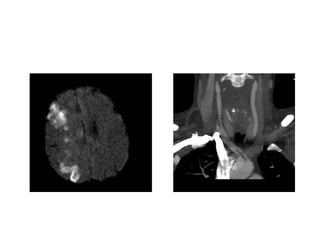

Multimodal Imaging

Multimodal CT

• Typically includes non-

contrast CT, perfusion CT,

and CTA

• Two types of perfusion CT

– Whole brain perfusion CT

– Dynamic perfusion CT

Multimodal MRI

• Standard MRI sequences

(T1 weighted, T2 weighted,

and proton density) are

relatively insensitive to

changes in cerebral

ischemia

• Multimodal adds diffuse-

weighted imaging (DWI)

and PWI (perfusion-

weighted imaging)

Multimodal Imaging Multimodal CT •Typically includes non- contrast CT, perfusion CT, and CTA • Two types of perfusion CT – Whole brain perfusion CT – Dynamic perfusion CT Multimodal MRI • Standard MRI sequences (T1 weighted, T2 weighted, and proton density) are relatively insensitive to changes in cerebral ischemia • Multimodal adds diffuse- weighted imaging (DWI) and PWI (perfusion- weighted imaging)